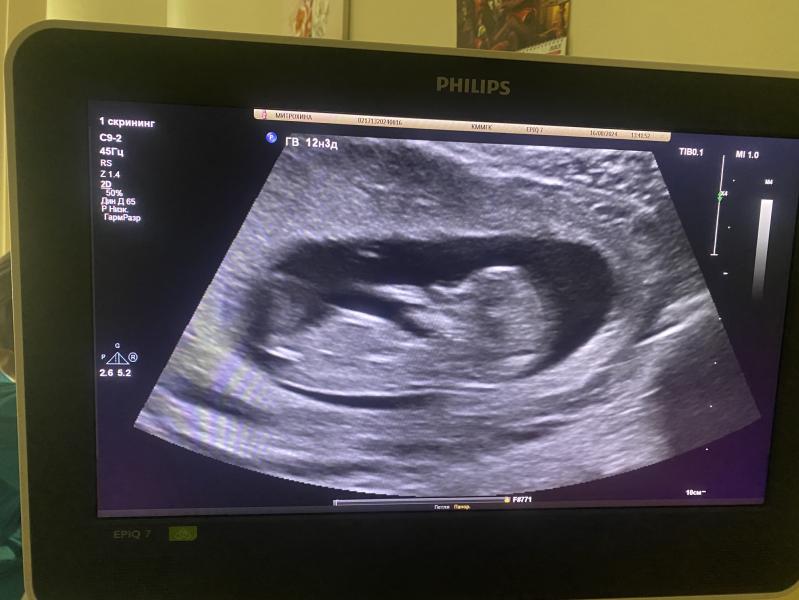

Ну вот и прошли первый скрининг🥰По узи все хорошо, ждём результат анализа крови🥰Мой голодный малыш сосал палец, вертелся крутился и всячески сбегал от датчика😁поэтому фото так себе😅Сказали что похожа на девочку🙈Я почему то до сих пор уверена что там мальчик😅

У вас мне кажется по бугорку , что девочка 🫣